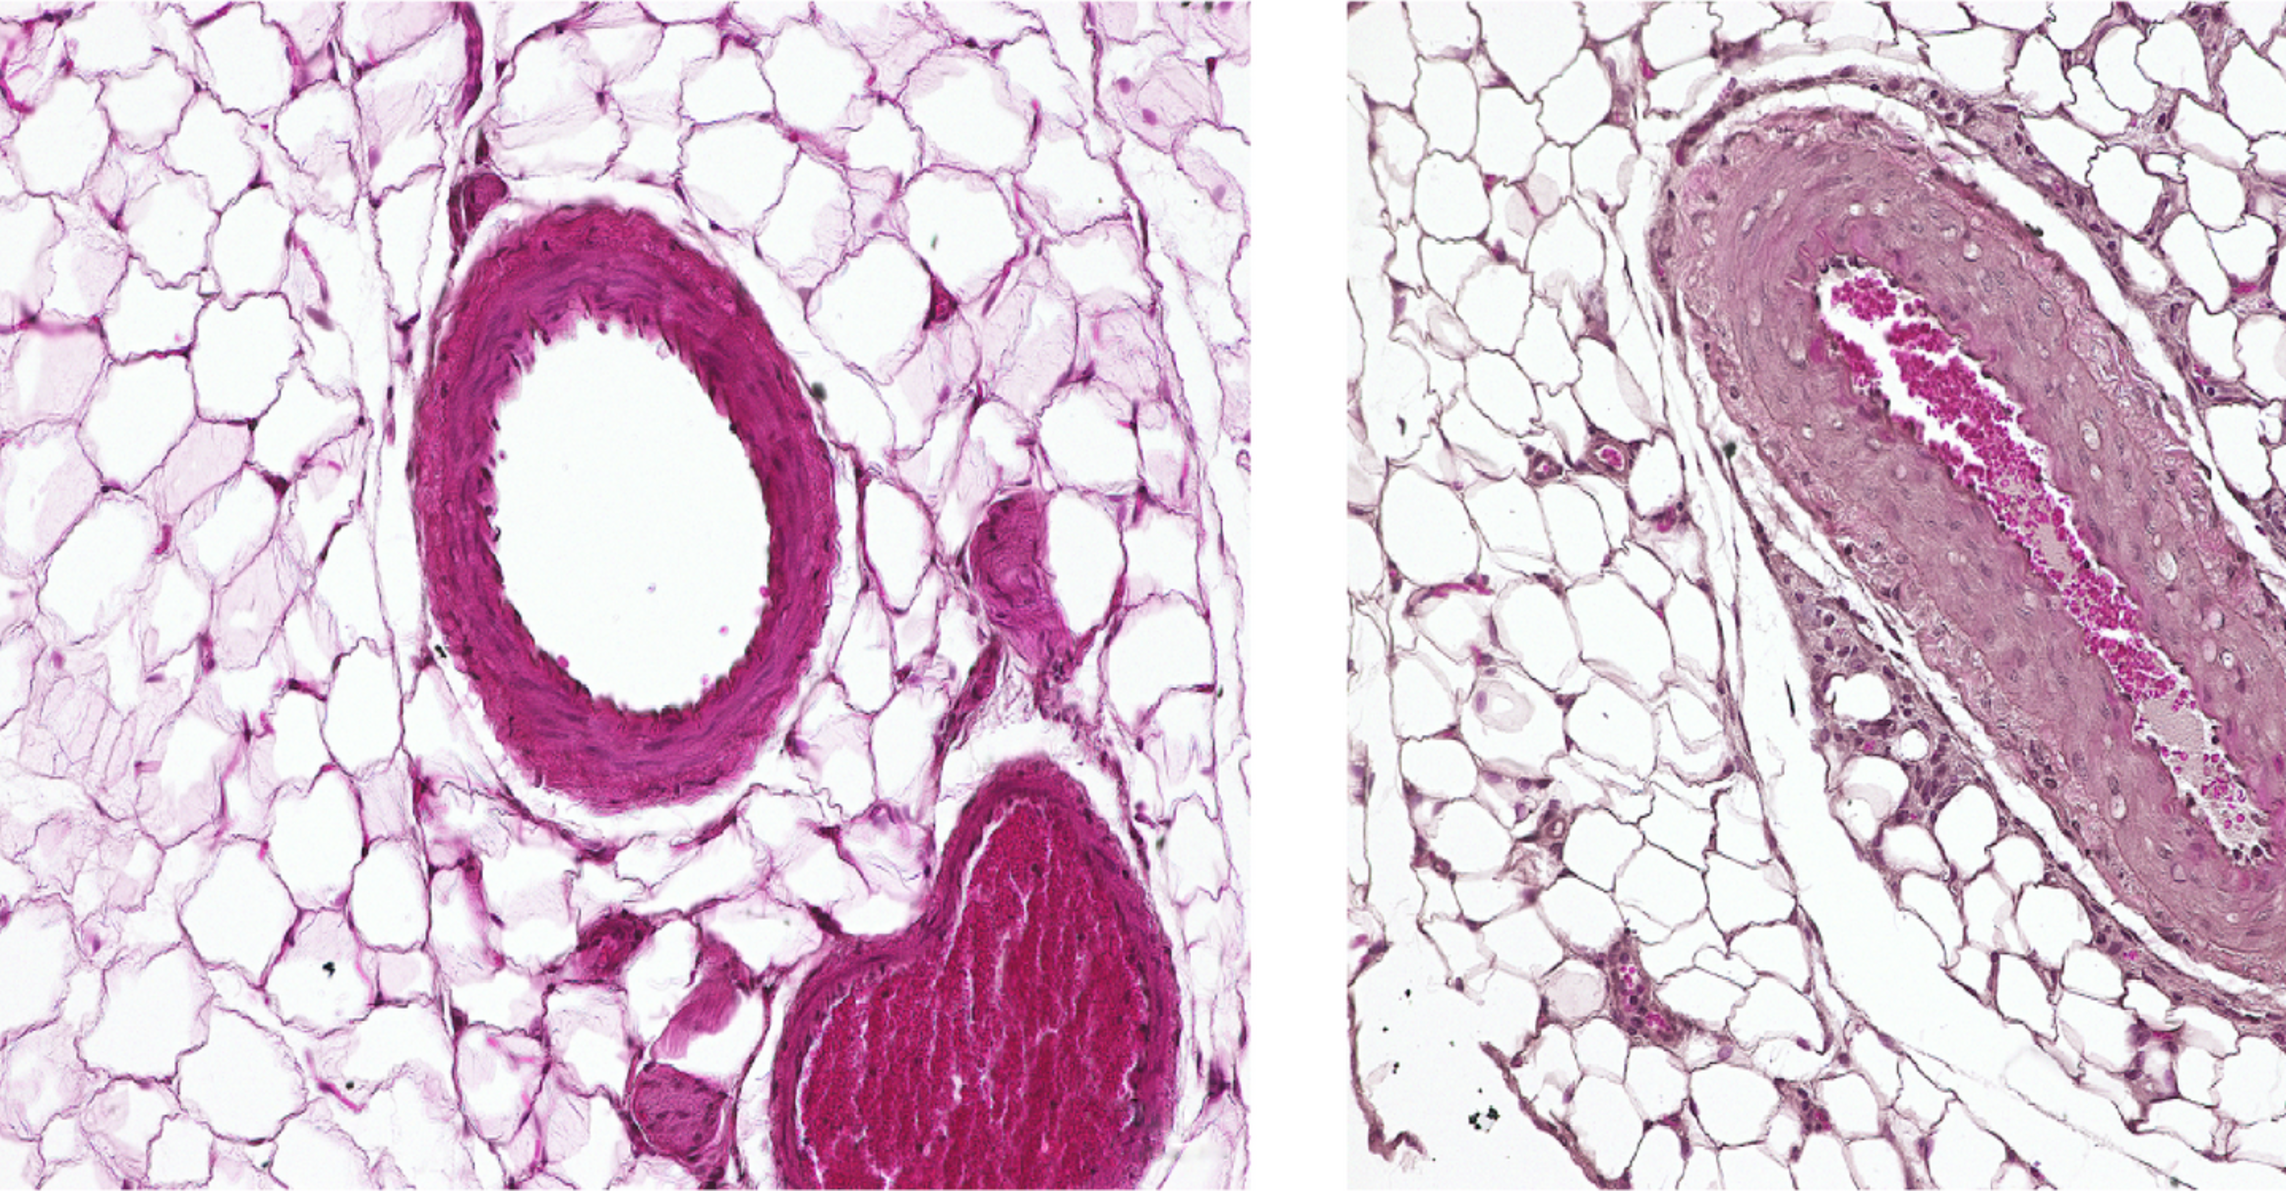

“We mainly worked with two animal models,” reports Dr. Lajos Markó, the paper’s co-lead author along with Maria Ercu. One of the models consisted of genetically modified mice in which the human enzyme PDE3A in the smooth muscle cells of the vessel walls was overactive due to the gene alteration. “These animals exhibited extremely high blood pressure as compared to the control animals,” Markó says.

Text: Anke Brodmerkel / Image: © Dr. Q. Fatimunnisa, Bader Lab, MDC